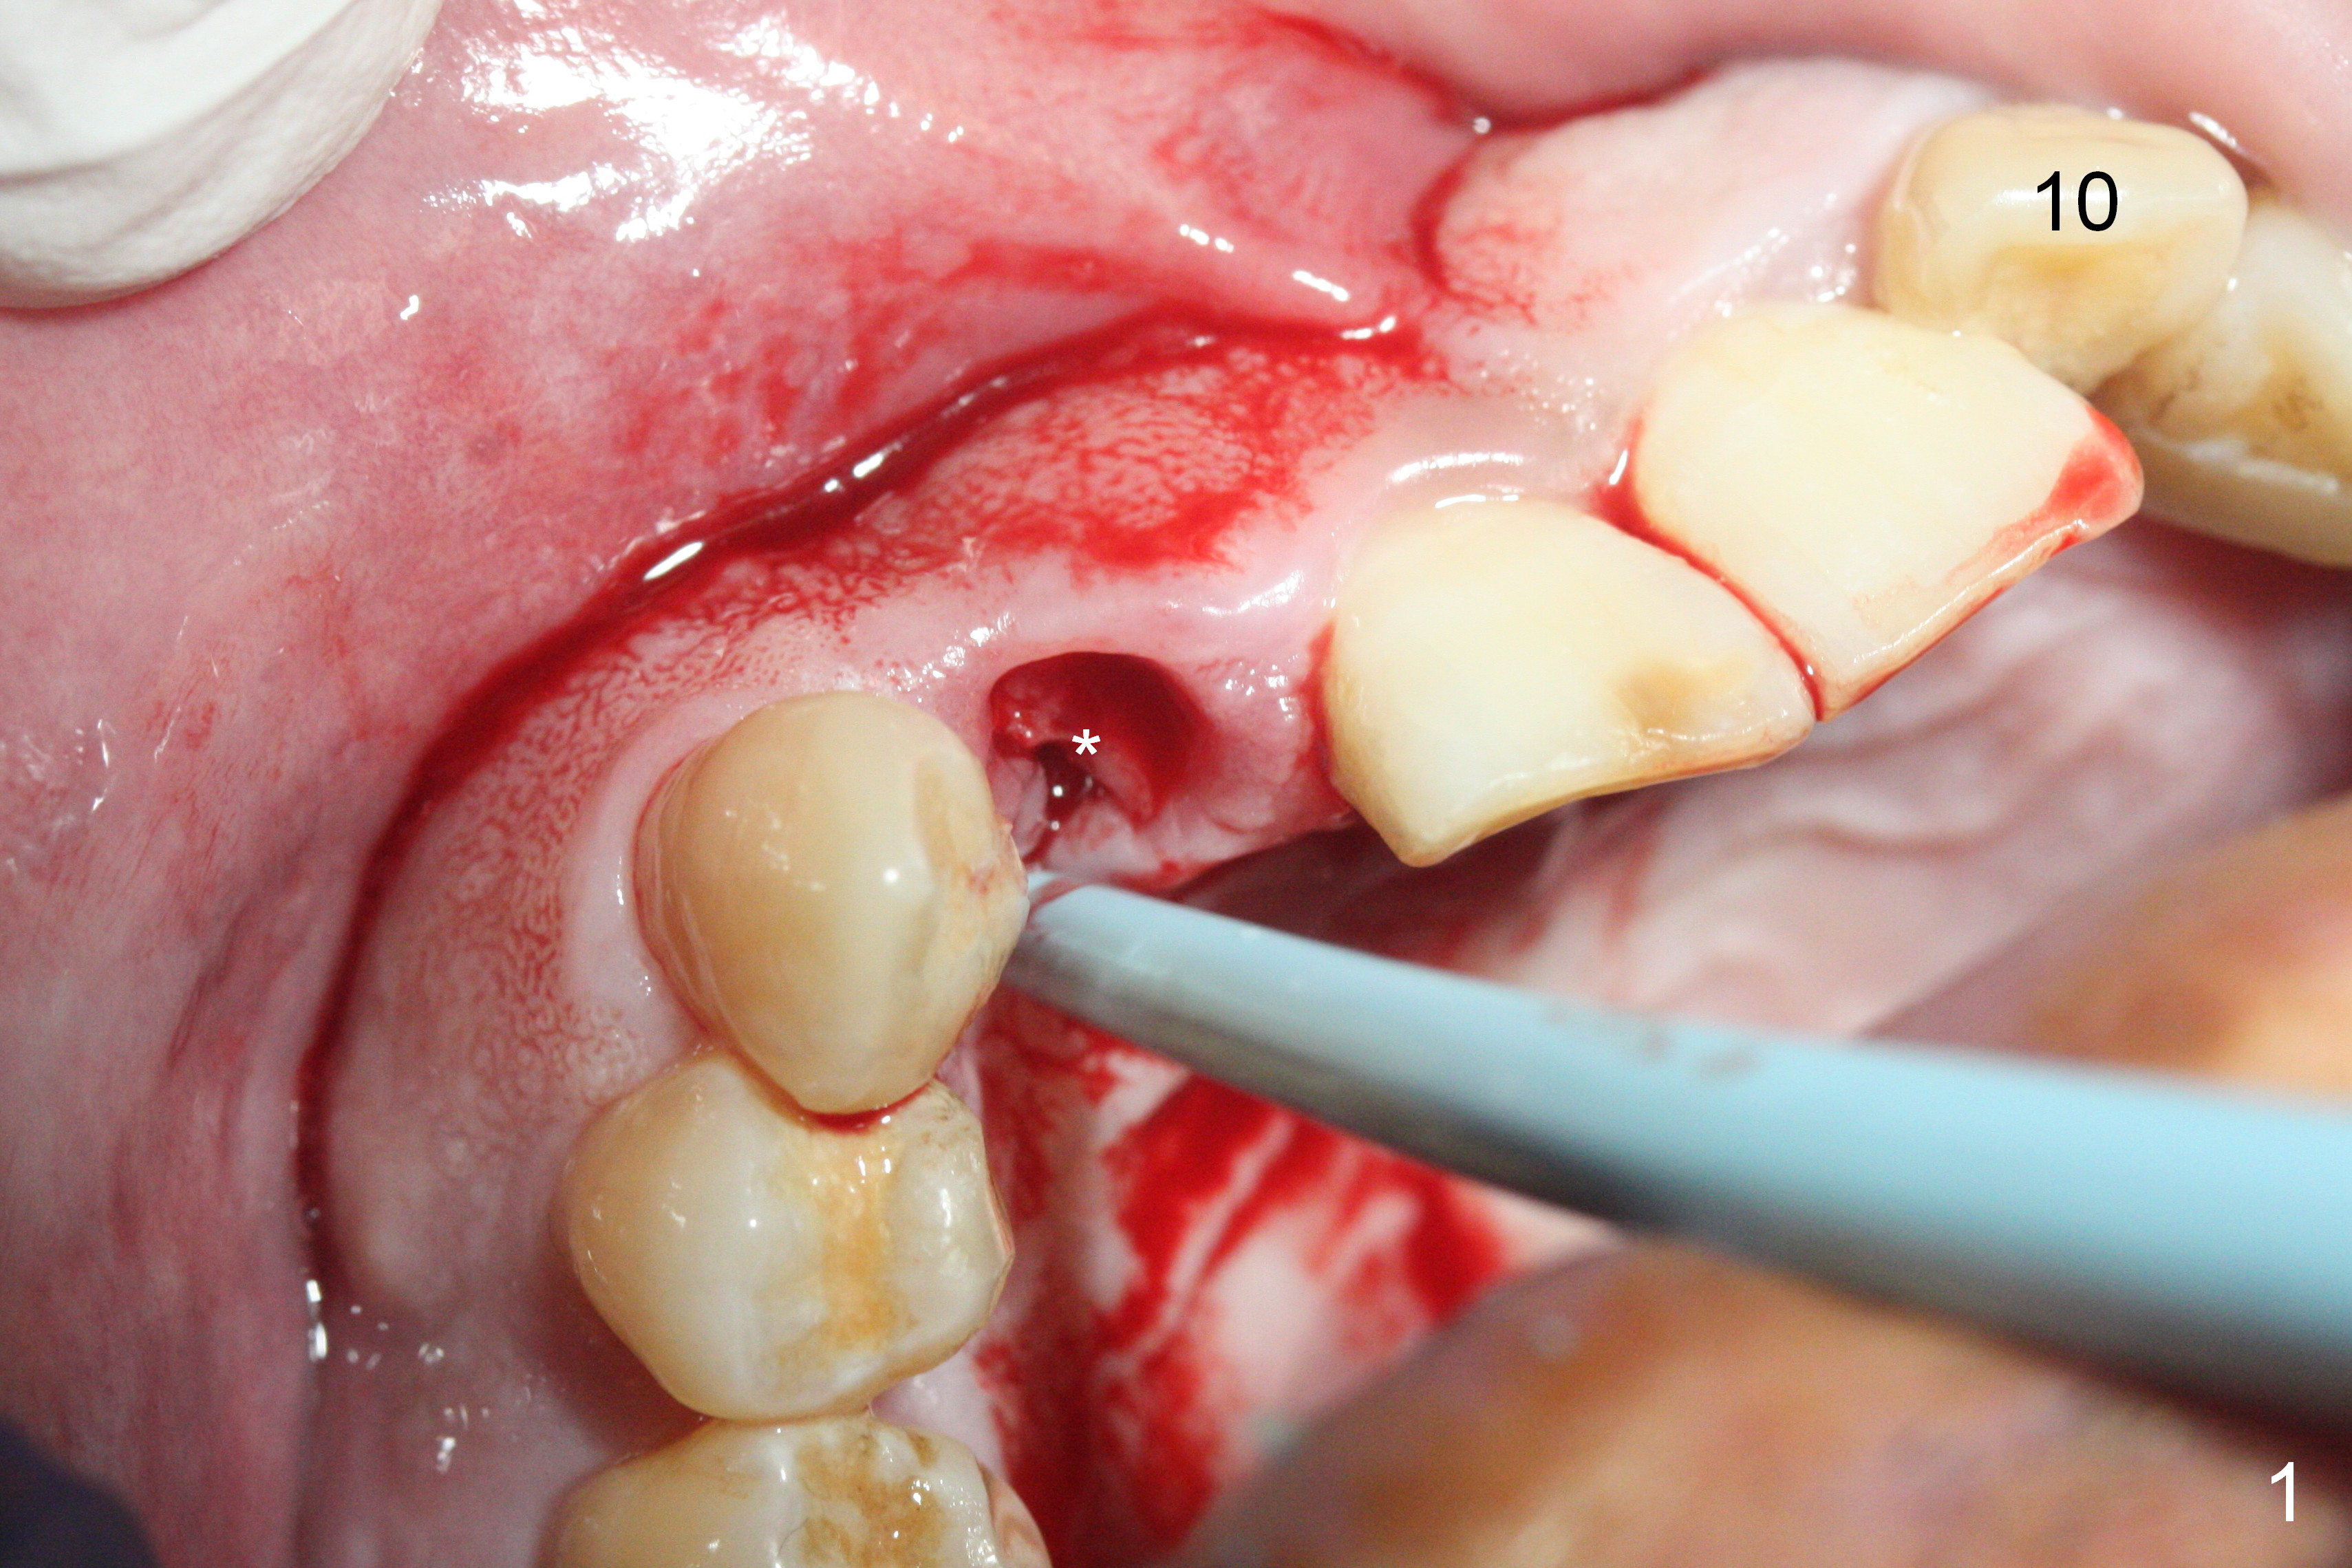

Access to the fractured root is limited after the crown is removed (Fig.1 *). Note the buccally-positioned tooth #10. After explanation the patient accepts in advance the possibility of the similar or same position of the restoration at #7.

Sixteen days postop, the patient is doing fine, although the labial fistula has not disappeared (Fig.8 <). The detached distolabial papilla is healing (Fig.9 *) with mild bone graft exposure (^). The lacerated distopalatal papilla is also healing (Fig.10 *). These complications are related to flap surgery. The apical portion of the socket appears to have reduced 4 months postop (Fig.14). When the definitive restoration is delivered 5 months postop, there is gingival recession, including the distal of #8 (Fig.11 arrows, which is expected to improve over time) due to flap surgery. The labial plate collapse is minimal (Fig.12 *), while the palatal laceration (Fig.10) has healed (Fig.13). When the patient returns 1.5 years post cementation, there is increased bone density next to the coronal portion of the implant, equivalent to the bone graft (Fig.15 *). The fistula is absent (Fig.16). The crestal bone loss remains 2.5 years post cementation (Fig.17 *), although there is no sign of periimplantitis (magnification). Oral hygiene is poor. There is no change in the soft (gingival recession; data not shown) or hard tissues 3 years 8 months post cementation (Fig.18).